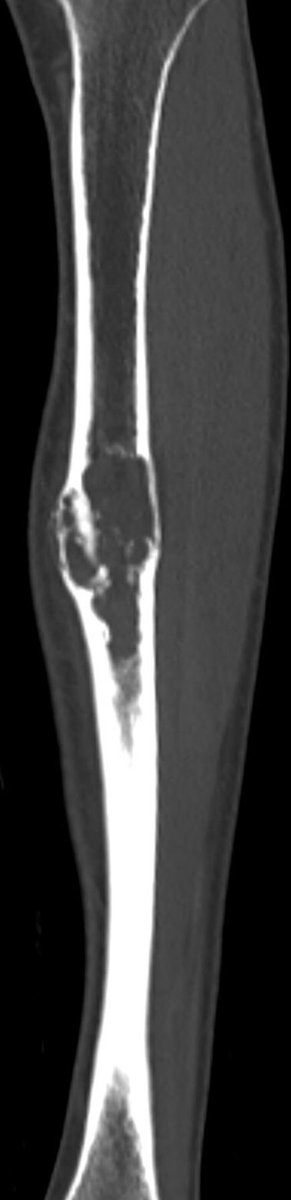

X ray of the tibia

Here a case of lower extremity pain

A single destructive lesion or multifocal tumour,may be identified, affecting cortex and often extending to the medulla,most commonly in the mid-tibial shaft.The lesion is typically eccentric and may cause mild bone expansion,endosteal scalloping and eventually destroy the cortex

AD typically appears multilocular and trabeculated, with intervening and surrounding sclerosis. A distinct periosteal reaction is unusual. An extra-osseous mass and pathological fracture may be seen

The tumour in the current case appeared to have arisen in the anterior cortex, extending inferiorly into both cortex and medulla, as a single focus of disease. The trabeculated appearance on radiographs appears to reflect the unusual extension of tumour through tibial cortex.

, with preservation of vertical ridges of cortical bone, surrounded by tumour, adjacent to areas of marked cortical thinning. Oedema-like hyperintensity on the bone surface suggests imminent fracture